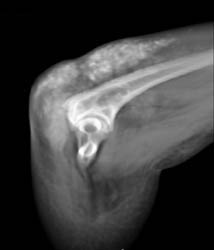

Gout